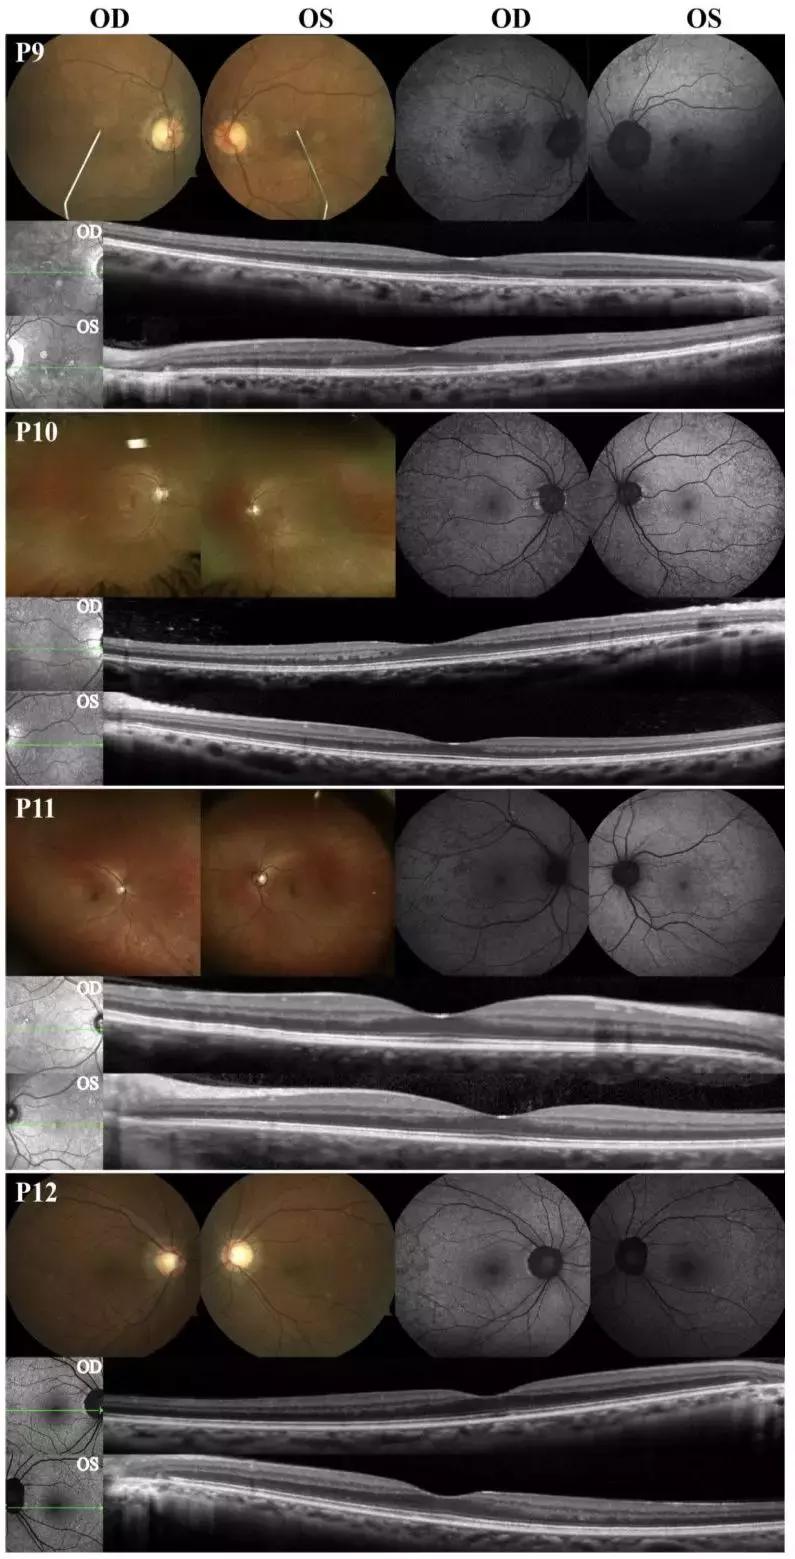

患者9-12表现为轻度,没有任何的视网膜脉络膜的萎缩,在眼底和AF下,后极部均可见斑点样的改变。OCT下可见完整的视网膜结构。患者9-12的结果见图3。

图3. 患者9-12的彩照,AF和OCT